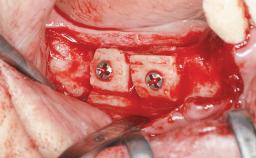

Le Fort I Interpositional Graft and Mandibular Sandwich Osteotomy for Maxillofacial Rehabilitation after Severe Periodontitis

A 47-year-old woman who had suffered from aggressive periodontitis requiring a number of periodontal interventions over more than 10 years was referred by her general dental practitioner and periodontologist for bone augmentation and implant therapy. Her failing dentition had already been scheduled for extraction. The patient expressed a desire for implant-supported fixed restorations and esthetic improvement of her lower face. She had agreed to consult with a maxillofacial surgeon after the referring dentist had suggested bone augmentation. An initial examination by the maxillofacial surgeon revealed mobility of all residual teeth in a patient who was very unhappy with the function of her removable partial dentures. Due to periodontally migrated flaring teeth and loss of occlusal support, the vertical dimension of occlusion was dramatically reduced. The patient was displeased with her lower face because of deepened nasolabial, commissural, and supramental folds.